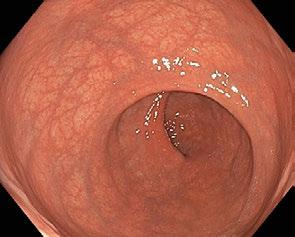

Obr. 1.1 Ampula rekta s příčnými rektálními řasami